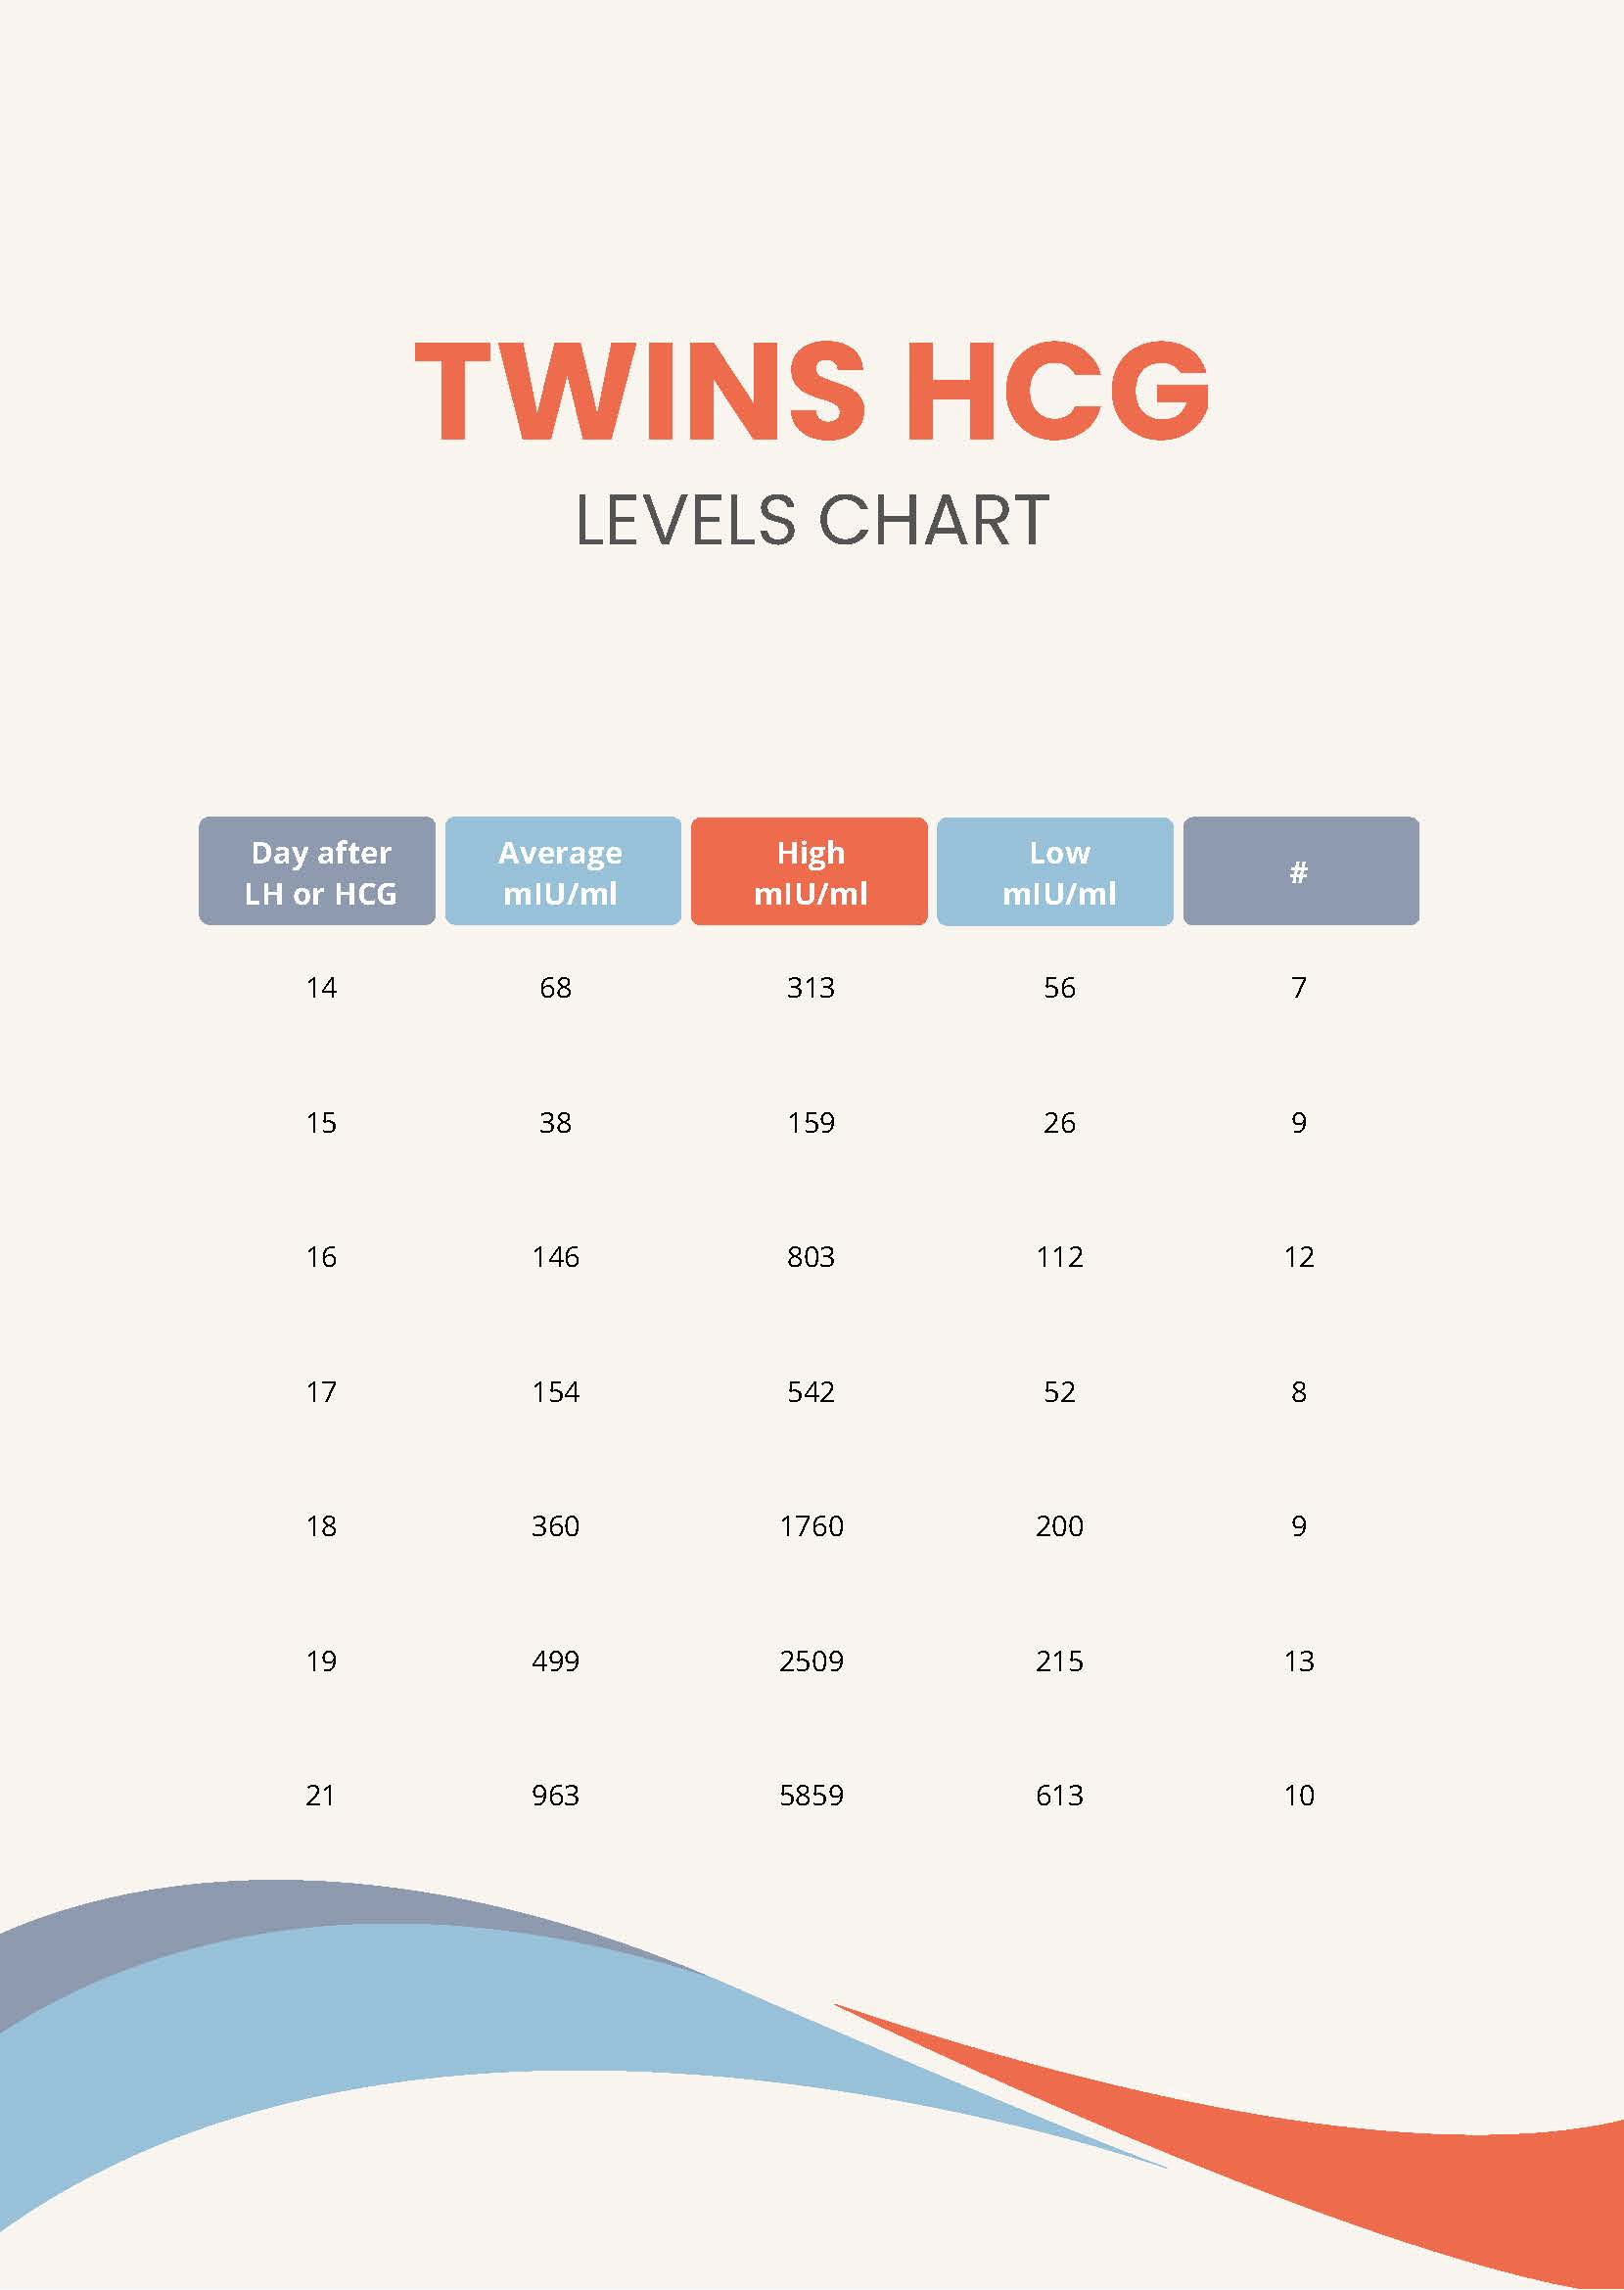

Hcg Levels Twin Pregnancy Chart